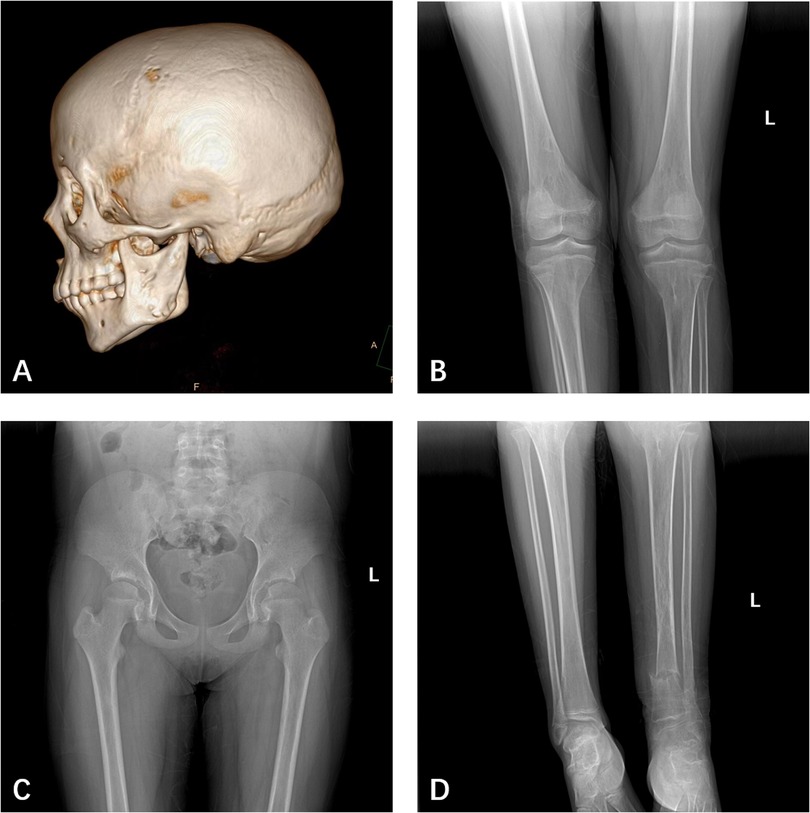

The patient, a 14-year-old female, experienced a fall while running. Initially, she complained of left leg and ankle pain and was unable to bear weight. However, she did not seek medical attention and continued with the weight-bearing activities, and her parents didn't notice the abnormality. After three months with persistent symptoms, she presented to a medical institution where an x-ray revealed a distal tibiofibular fracture. She underwent two months of cast immobilization followed by one month of external fixator fixation. No specify drug was intaken during this period. Follow-up x-rays showed nonunion at the fracture ends. Then she visited our outpatient clinic. Physical examination revealed facial asymmetry, multiple café-au-lait spots over her body, breast development, approximately 10° external rotation deformity of the distal left leg, limited active movement of the left ankle with pain on passive movement, and inability to bear weight independently (Figure 1). Comprehensive x-rays and CT scans identified nonunion of the left distal tibiofibular fracture in addition to the abnormal bone structure in the bilateral femurs, tibiae, left parietal bone and left mandible (Figure 2). Ultrasound revealed bilateral breast enlargement (Figure 3A) and enlarged uterus (Figure 3B), while thyroid (Figure 3C) and adrenal glands (Figure 3D) showed no abnormalities. Hematological hormone tests were normal (Table 1), as were whole exome sequencing tests, which showed negative results. Based on clinical examination and laboratory findings, she was diagnosed with MAS.

Figure 2. (A) CT showed bone abnormalities in the left parietal bone, and left mandible. (B) X-ray showed bone abnormalities in both femurs, tibia, and fibula. (C) X-ray showed bone abnormalities in both femurs, but not the iliac bone. (D) X-ray showed the left distal tibia and fibula fractures and nonunion.